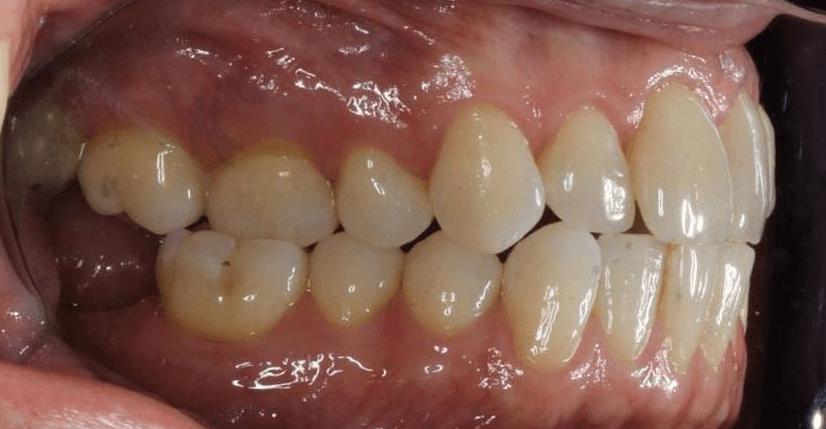

Diganosis: Minor and moderate crowding, anterior open bite, reverse smile arc, narrow maxilla, crossbite, tapered arch form

Adjuncts: Class III elastics, attachments, IPR

Final results

INTRAORAL